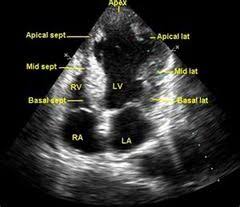

심장은 2개의 심방과 2개의 심실 4개의 판막 등으로 이뤄진 복잡한 구조로 돼있으며 1분에 평균 60회 이상 수축과 이완을 반복한다고 한다.

심장 초음파는 인체에 무해한 초음파를 이용해 실시간으로 이러한 심장의 움직이는 모습을 관찰할 수 있고 심장의 움직임과 구조, 혈류의 흐름, 판막의 이상 유무 등을 비침습적으로 관찰할 수 있는 검사법이라고 한다. 대부분의 심장 질환에 필수적인 검사며, 많은 심장질환에서 높은 정확도를 가진다고 한다.

심장 초음파를 통해 심장근육의 손상여부나 좌심실 벽의 두께 등을 관찰해 협심증, 심근경색 등을 알아낼 수 있다고 한다.